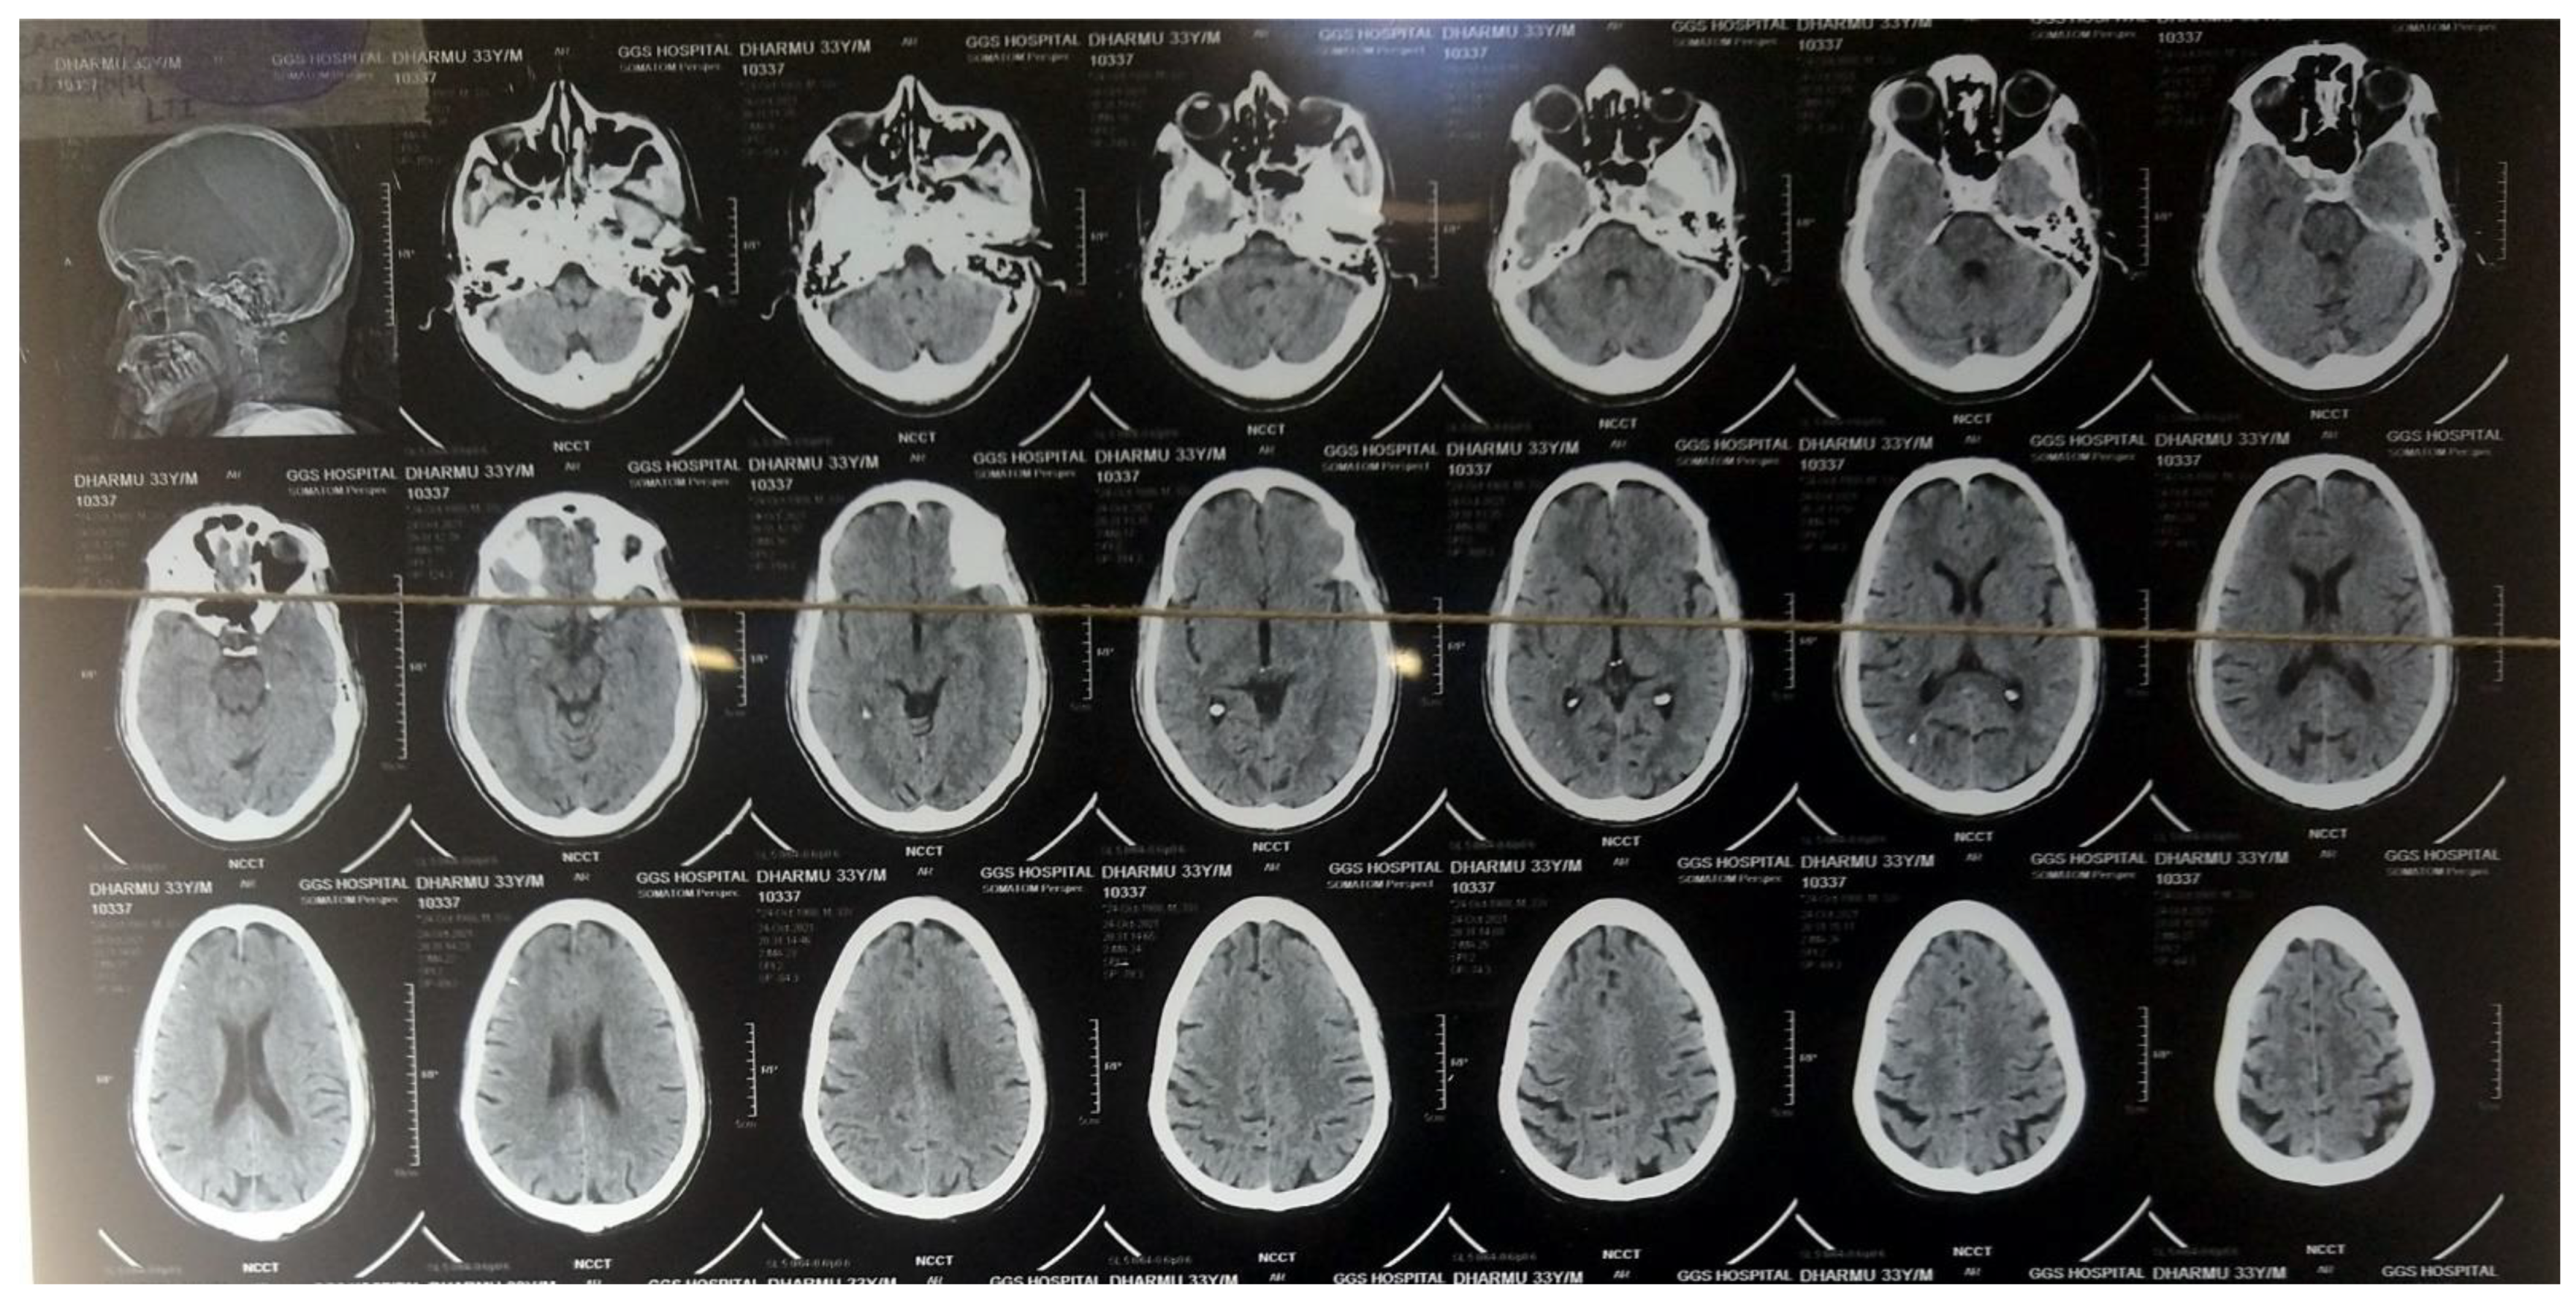

2. Case Presentation

3. Investigations